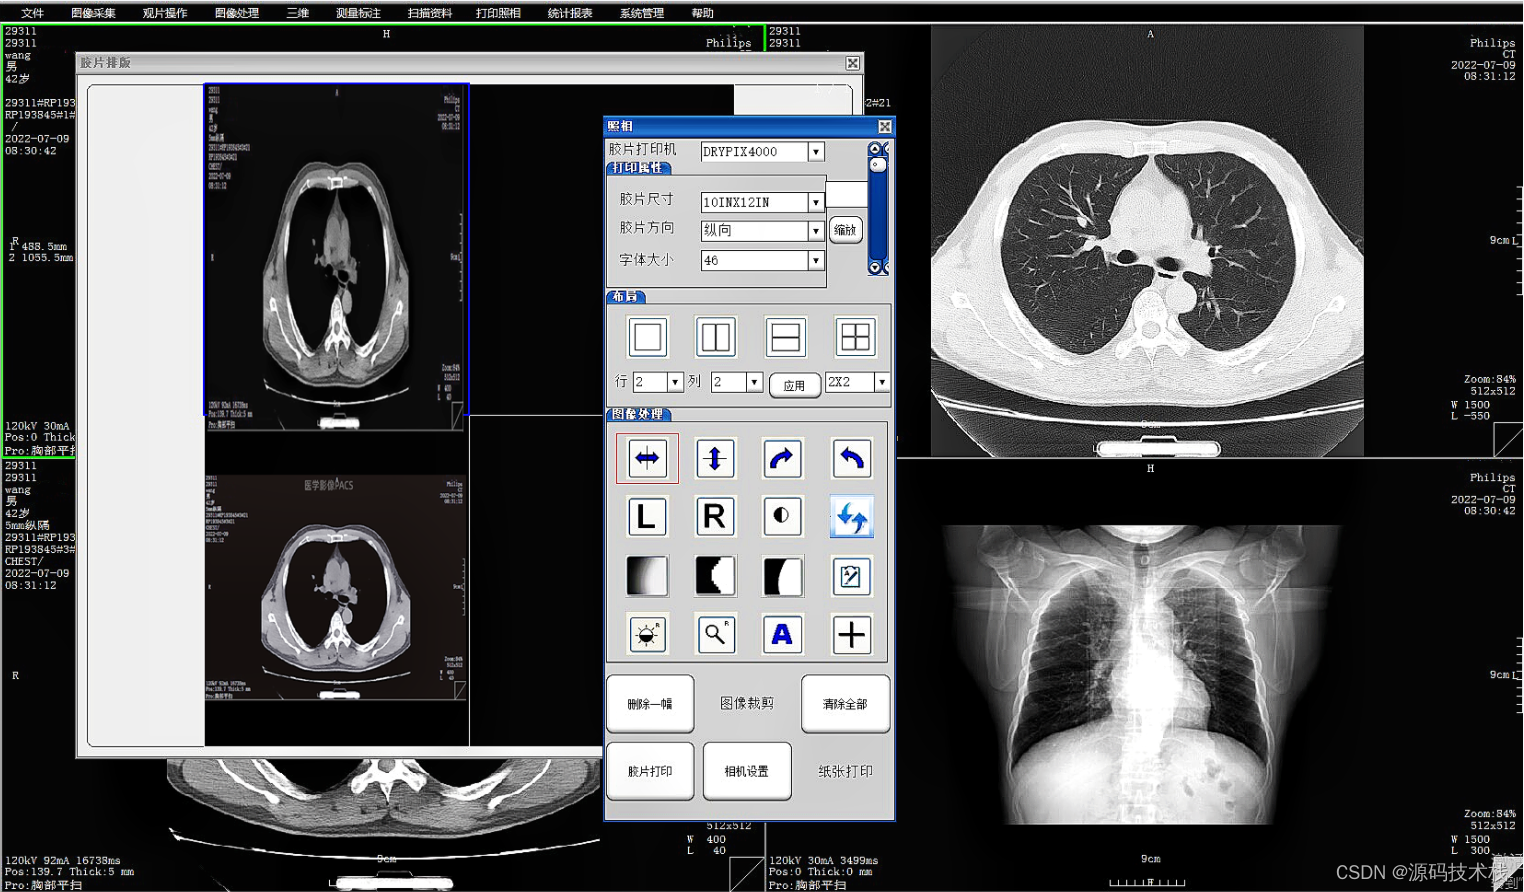

·提供胶片打印功能,多种影像排列和影像组合方式输出。

(7)图像后处理与重建

·MPR\CPR(三维多平面重建)

·VRT(三维容积重建)